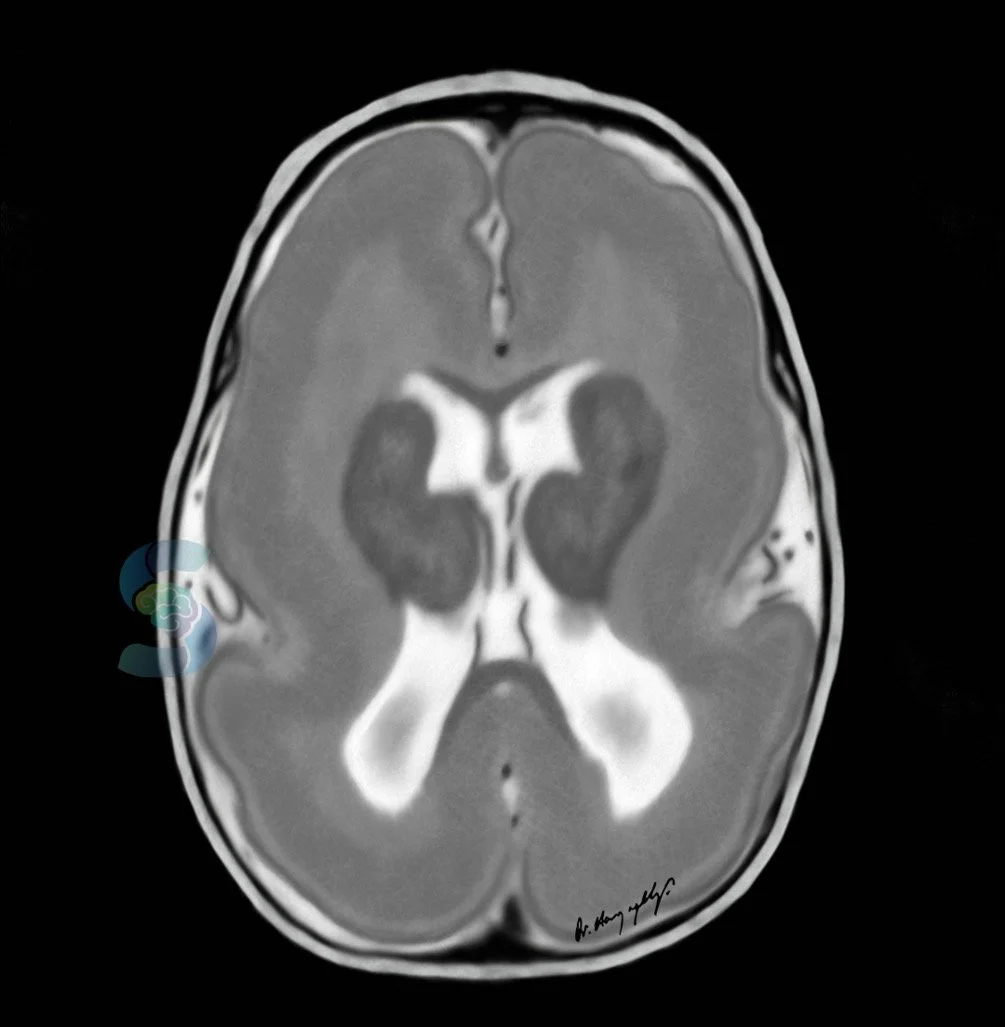

Huntington’s disease

atrophy of caudate head causes enlargement of frontal horns